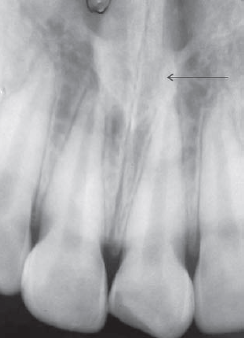

63. What arrow shows?

Nasolabial Fold An oblique line demarcating a region that appears to be covered by a veil of slight radiopacity frequently traverses periapical radiographs of the premolar region. The line of contrast is sharp, and the area of increased radiopacity is posterior to the line.